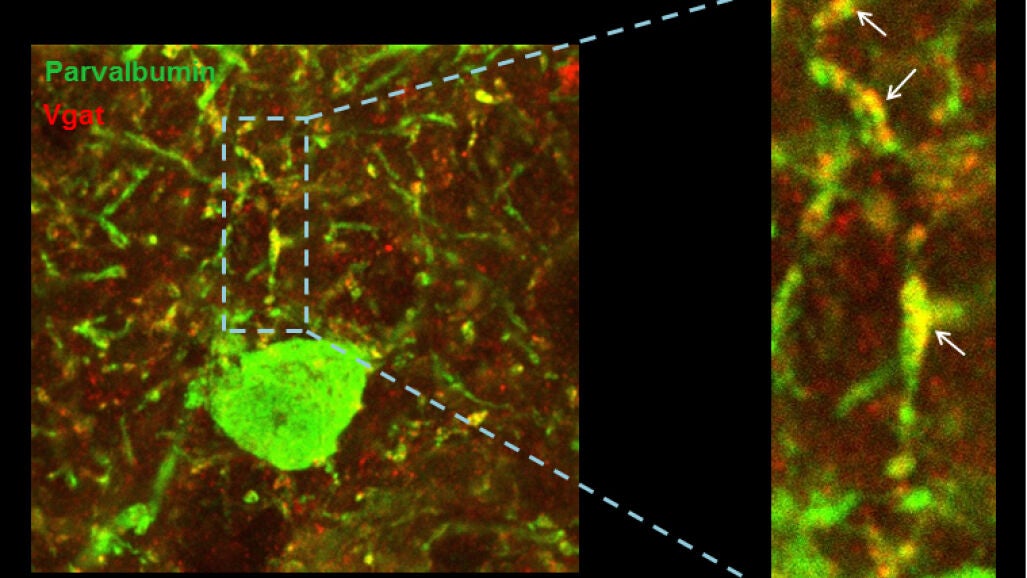

Las científicas se han centrado en uno de los genes relacionados con el síndrome de Down. Mediante experimentos con modelos animales que sobreexpresan el gen candidato, demostraron que el exceso de este gen provoca cambios muy sutiles en el equilibrio excitación/inhibición y estos llevan a una reducción notable de la actividad y sincronización de las neuronas excitadoras en la corteza prefrontal.

Es decir, que cuando este gen se encuentra sobreexpresado, reduce el nivel de descarga de las neuronas y altera el ritmo en las ondas de alta frecuencia de la corteza cerebral. Es más, observaron que el problema radica en unas neuronas que se encargan de controlar la inhibición. En resumen, si hay menos actividad y existe una desequilibrio en las frecuencias de las ondas cerebrales en síndrome de Down es debido a cambios en la conectividad de las neuronas que deben controlarlas.